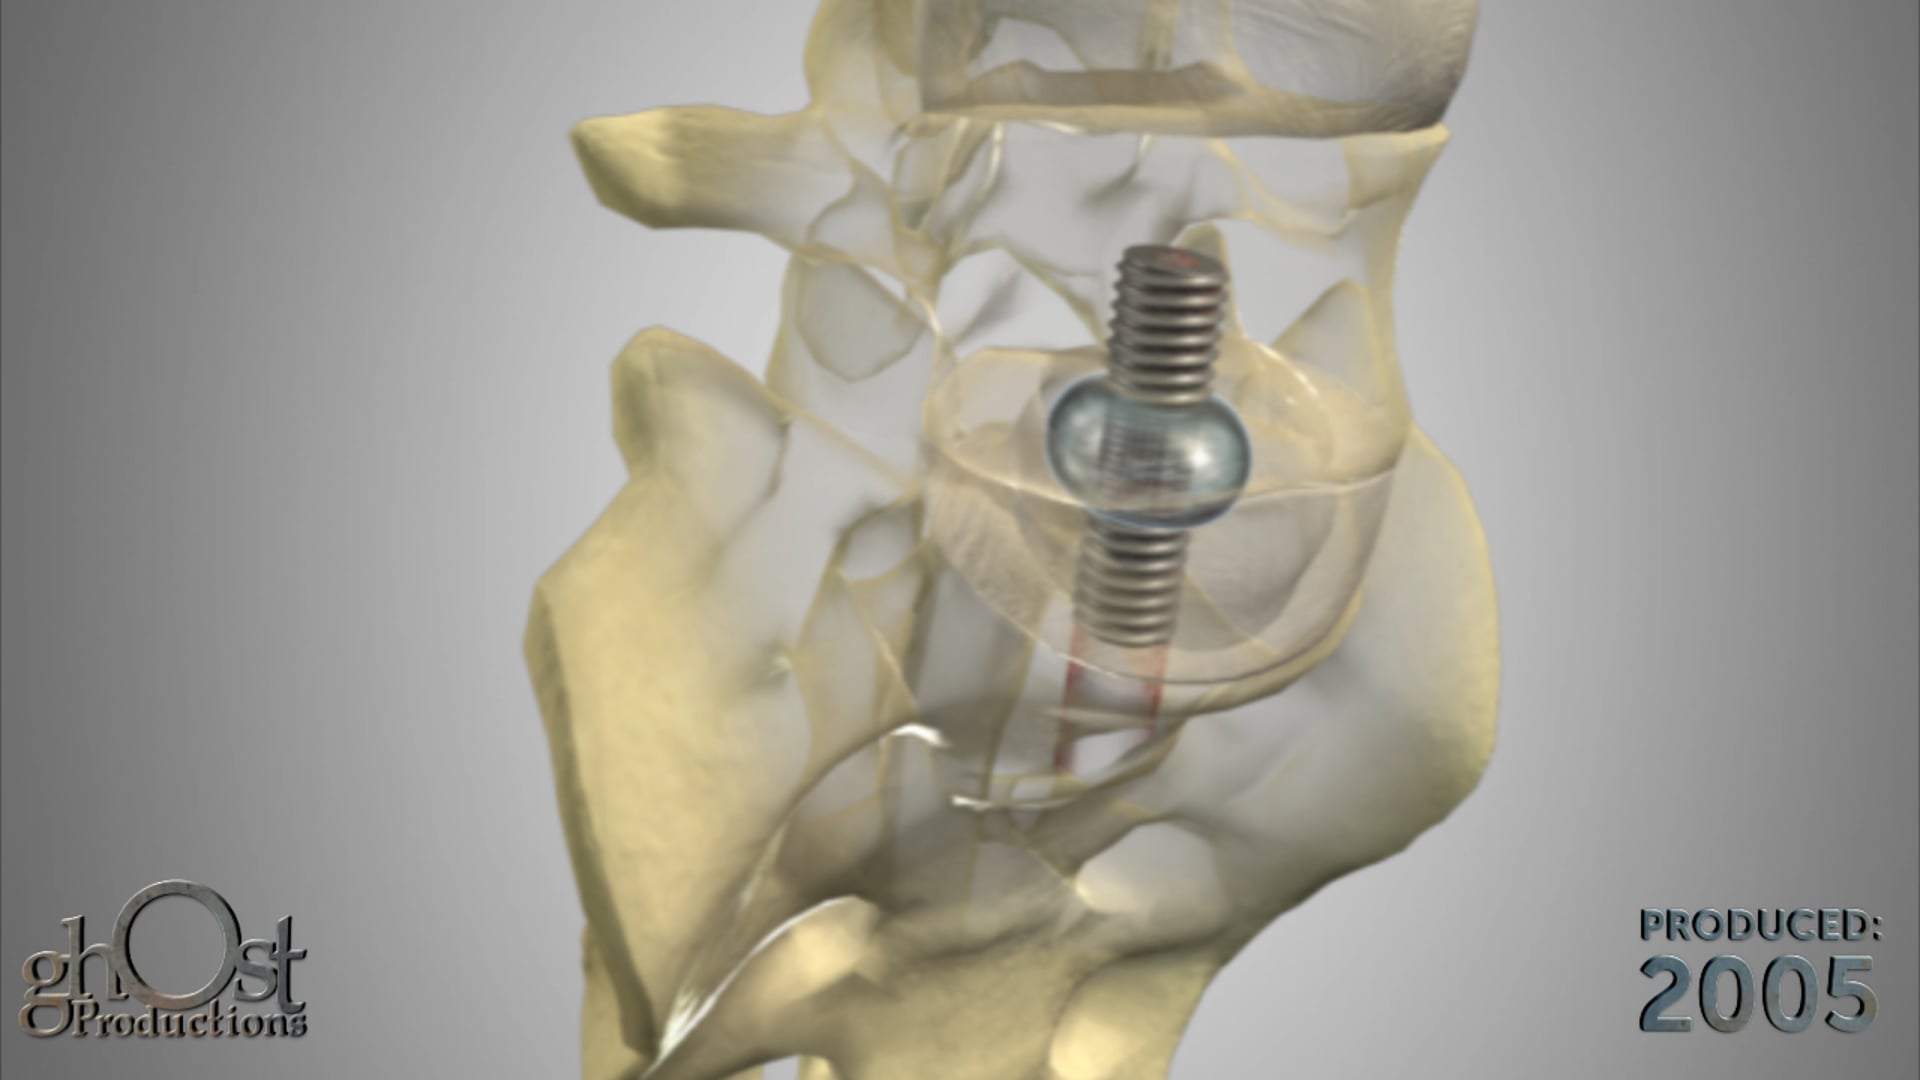

Ghost Productions' animation showcases the Keo Brace, a revolutionary device for Carpal Tunnel Syndrome treatment, providing support to the wrist and reducing pressure on the median nerve. Medically accurate and informative, it's a must-see for healthcare professionals and patients.

Ghost Productions has produced a visually stunning animation that highlights the Keo Brace, a revolutionary device used in the treatment of Carpal Tunnel Syndrome. This video showcases the Keo Brace's unique design and its ability to alleviate the symptoms of Carpal Tunnel Syndrome by providing support to the wrist and reducing pressure on the median nerve. The animation is medically accurate and provides a detailed explanation of how the Keo Brace works, making it an invaluable resource for healthcare professionals and patients alike. This video is a must-see for anyone interested in the latest advancements in the treatment of Carpal Tunnel Syndrome.

The animations showcased by Ghost Medical are intended solely to demonstrate our portfolio work and are not intended to be labeled as reliable FDA claims in the healthcare market. Surgeons and healthcare professionals should exercise caution and conduct their own research before relying solely on the information presented in the animations. Please be aware that while our animations strive to accurately represent medical concepts and technologies, they may not always reflect the current state of the medical industry.